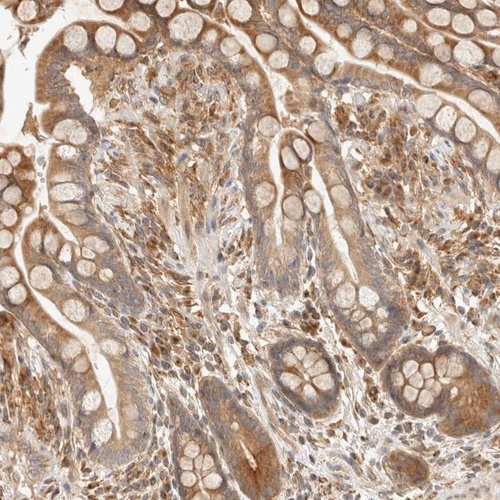

Immunohistochemical staining of human colon shows moderate cytoplasmic positivity in glandular cells.